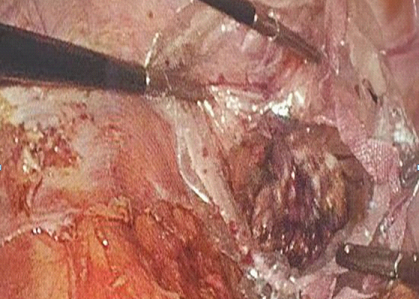

▲手术操作中

腹腔镜NOSES直肠癌根治术后一天就可以自由行走,因为下床活动早,可以避免动、静脉血栓的发生,因为疼痛轻、咳痰易,大大降低肺部感染的出现,这些优势都为直肠癌患者带来了福音。